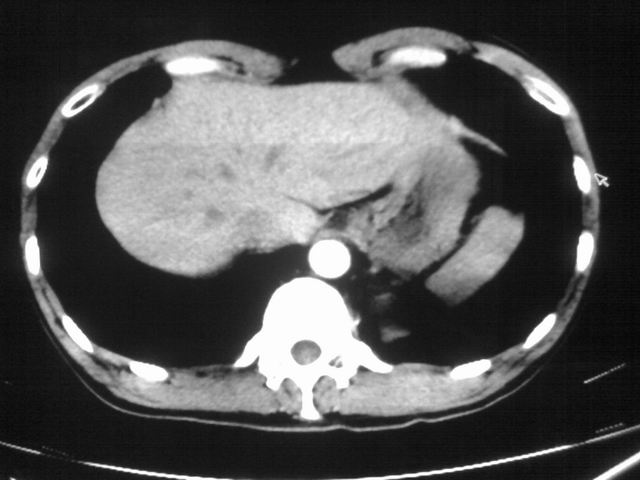

以下是引用苯小孩在2007-4-24 19:46:00的发言:[br]左下肺内侧基底段,见类圆形病灶,边缘清晰光滑.强化后轻中度强化.<平扫第4层面似有从腹主动脉相连血管影,可惜强化扫描这层没有抓住>考虑:左下肺隔离症.建议dsa或薄层强化重建观察.

以下是引用同在2007-4-24 20:11:00的发言:[br]考虑肺隔离症